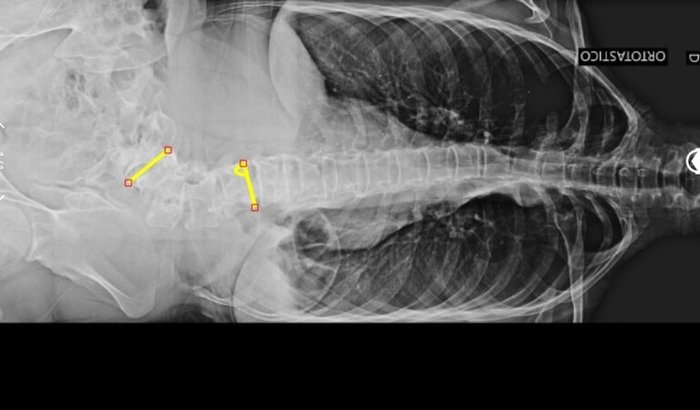

Olá, eu sou a Samily Gabrieli Queiroz Teixeira, tenho 18 anos e fui diagnosticada com Escoliose Congênita (Malformação Vertebral) e Síndrome de Marfan de alto grau.

Minha deformidade é classificada como grave, apresentando 65 graus de tortuosidade, o que causa dores constantes (nível 8/10), prejudicando minha qualidade de vida, equilíbrio postural e bem-estar psicológico.

Olá, eu sou a Samily Gabrieli Queiroz Teixeira, tenho 18 anos e fui diagnosticada com Escoliose Congênita (Malformação Vertebral) e Síndrome de Marfan de alto grau.

Minha deformidade é classificada como grave, apresentando 65 graus de tortuosidade, o que causa dores constantes (nível 8/10), prejudicando minha qualidade de vida, equilíbrio postural e bem-estar psicológico.